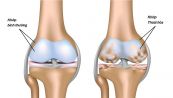

Chấn thương dây chằng chéo trước là tình trạng căng hoặc rách dây chằng. Tùy thuộc vào tình trạng nghiêm trọng và mức độ hoạt động, rách dây chằng có thể một phần hoặc hoàn toàn. Để hiểu rõ hơn về bệnh chấn thương này, mời các bạn tham khảo bài viết dưới đây!

Chấn thương dây chằng đầu gối có thể khiến bạn rất đau và hạn chế những hoạt động thường ngày. Bài viết dưới đây sẽ nói rõ hơn về triệu chứng, nguyên nhân và cách điều trị của chấn thương dây chằng đầu gối, mời các bạn tham khảo.